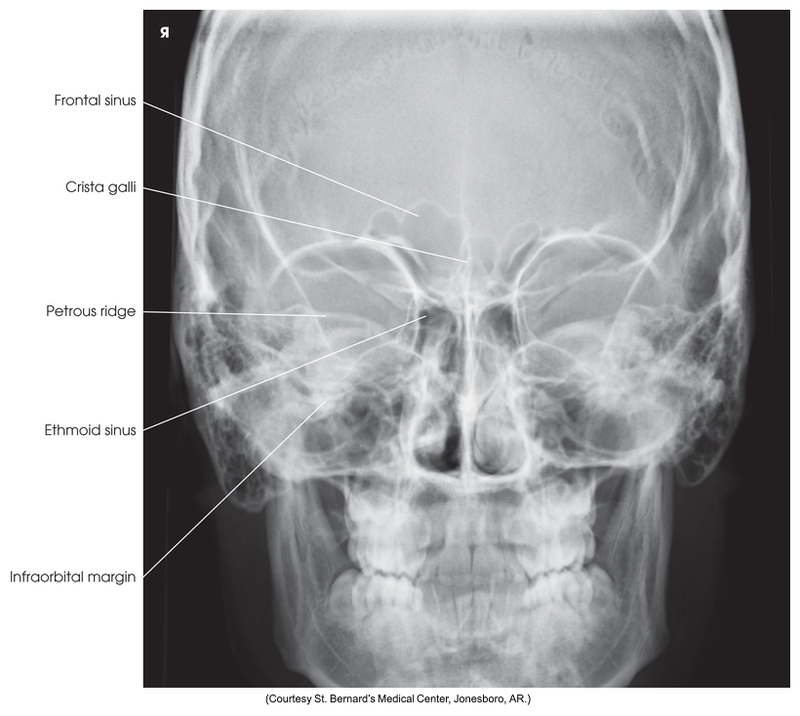

PA axial of facial bones - Caldwell Method

PA Axial of the Frontal and Ethmoidal Sinuses - Caldwell Method

PA axial skull - Caldwell Method

PA axial of facial bones - Caldwell method

PA axial of the frontal and ethmoidal sinuses (Caldwell Method)